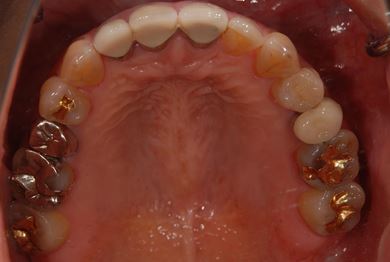

主訴 右下の奥歯をセラミックで治療したい。

治療内容 メタルボンドセラミック(クラウン1本、ブリッジ3本、メタルボンドセラミック土台1本)+ハイブリッドセラミックインレー1本

治療前

• 治療前